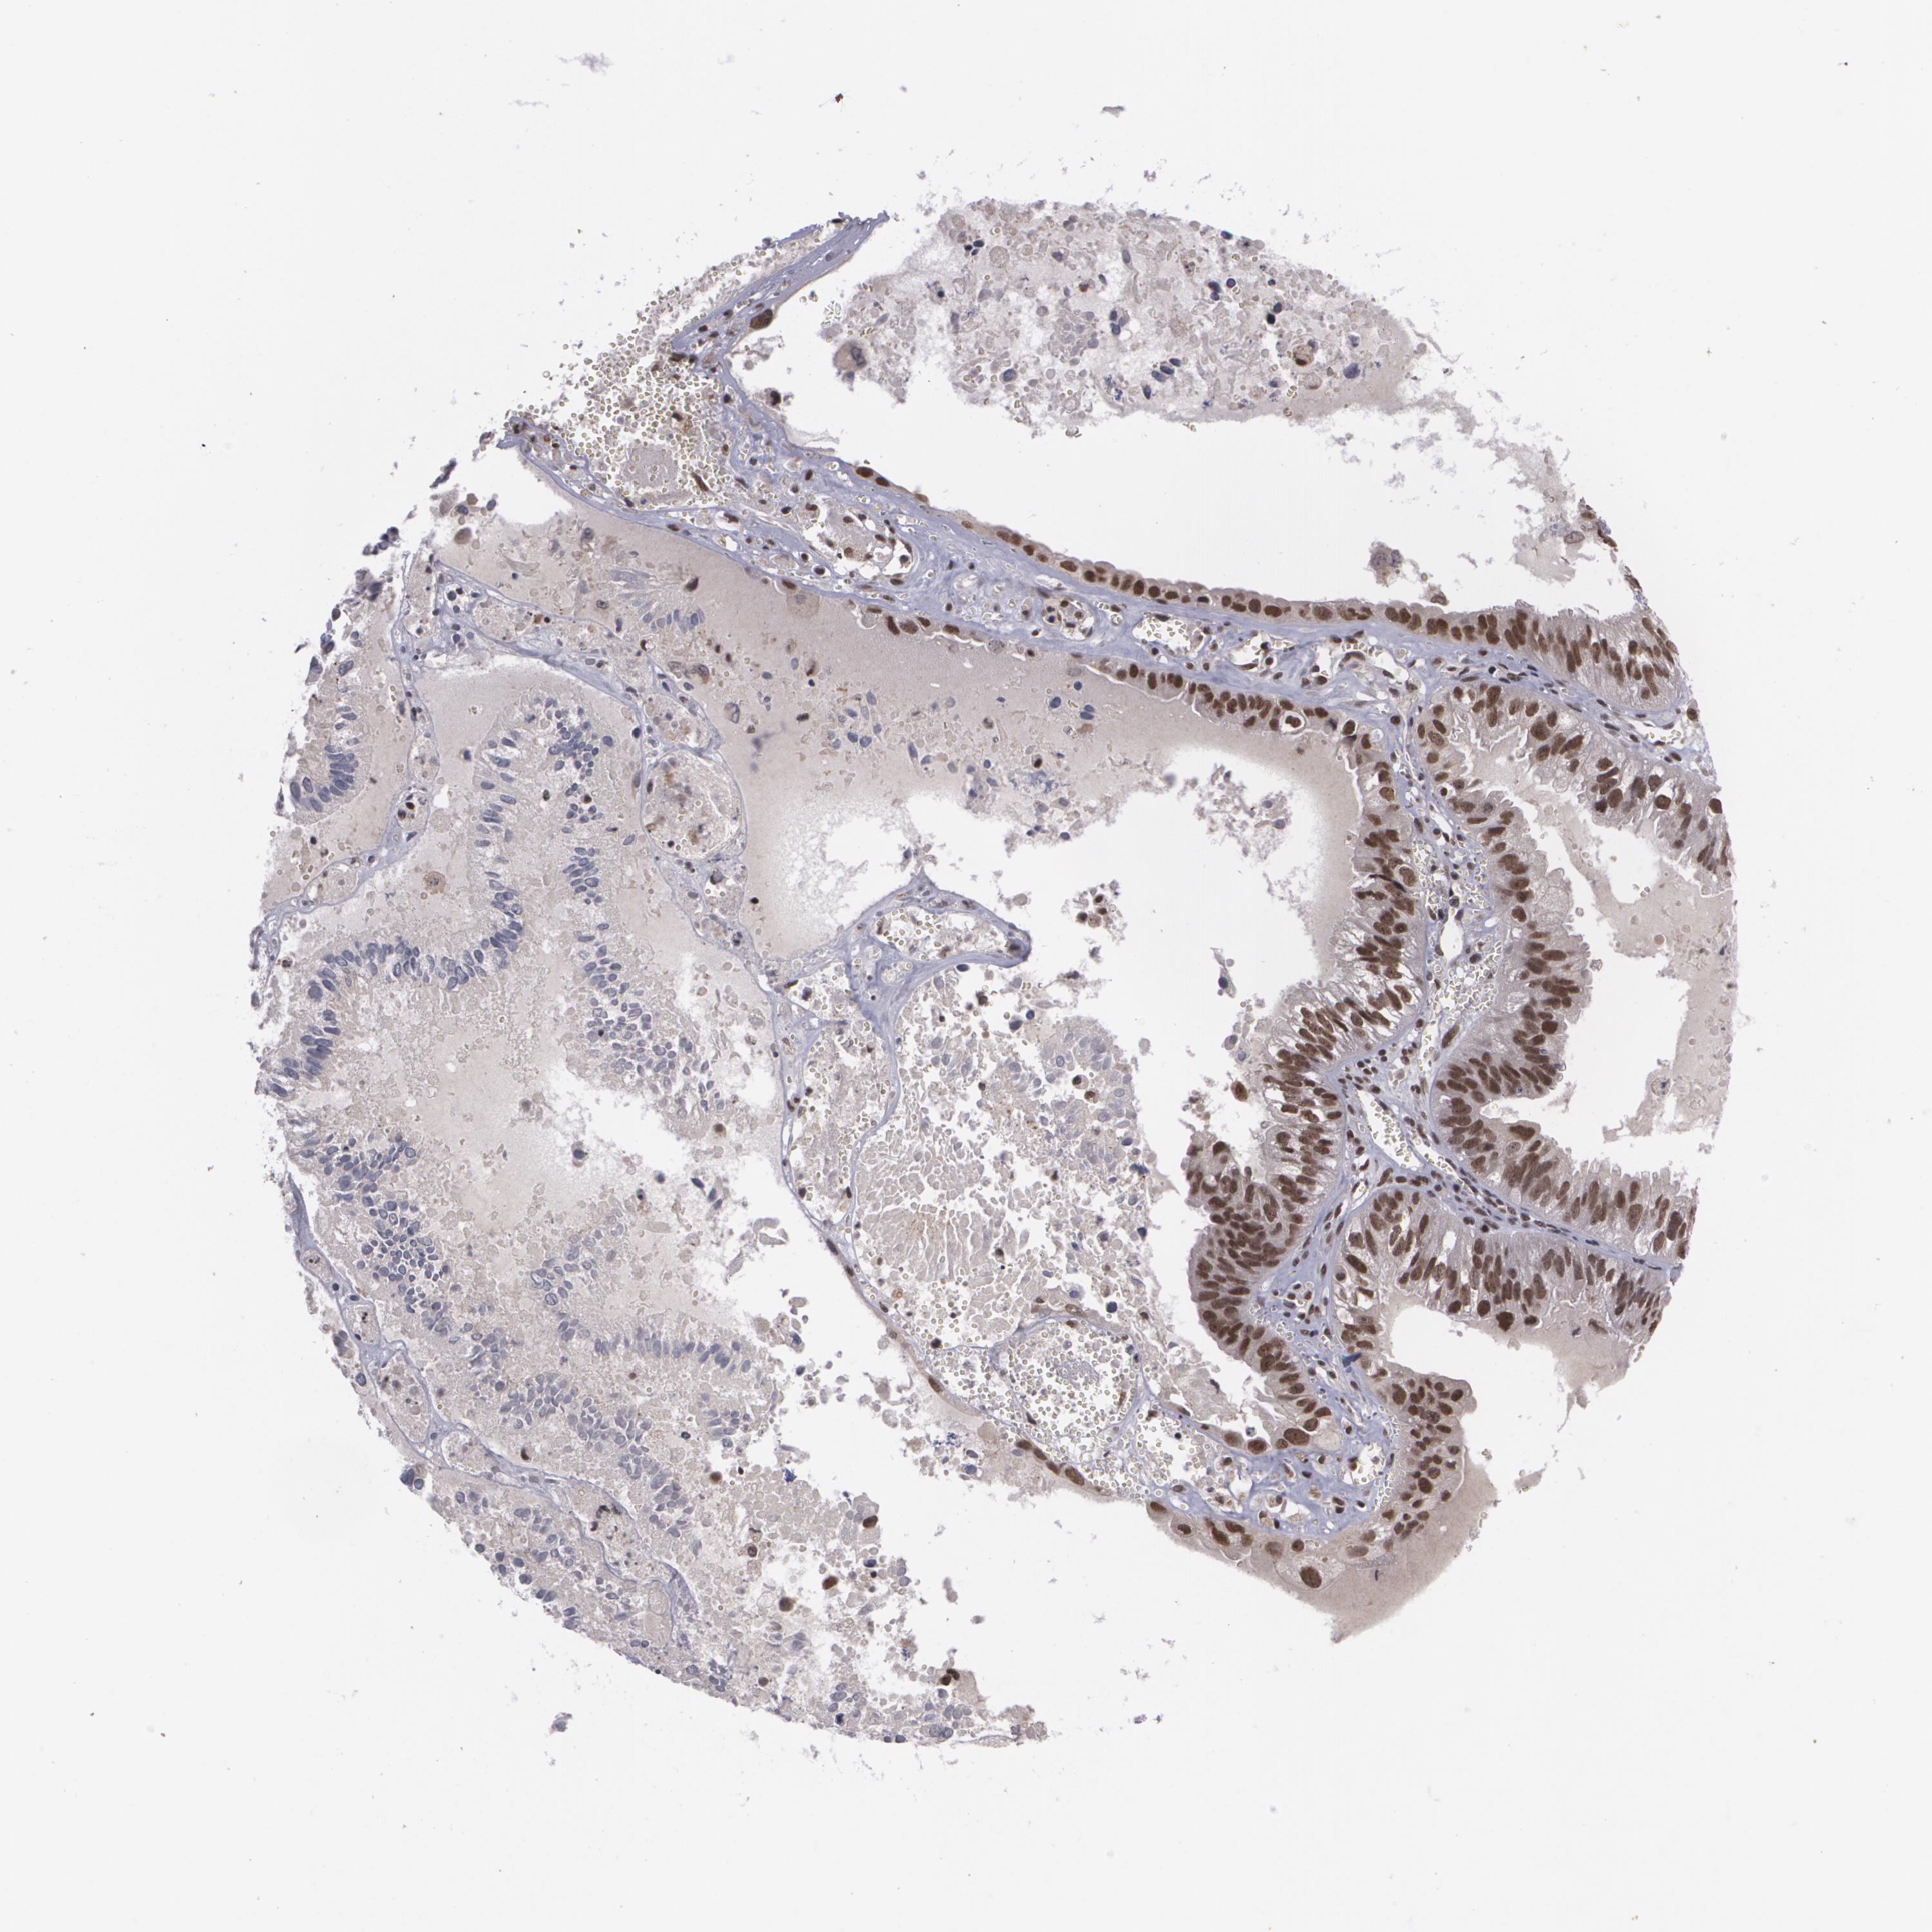

OVARIAN CANCER - Protein expressioni

A mouse-over function shows sample information and annotation data. Click on an image to view it in a full screen mode. Samples can be filtered based on level of antibody staining by selecting one or several of the following categories: high, medium, low and not detected. The assay and annotation is described here.

Note that samples used for immunohistochemistry by the Human Protein Atlas do not correspond to samples in the TCGA dataset.

Antibody stainingi

Antibody staining in the annotated cell types in the current human tissue is reported as not detected, low, medium, or high, based on conventional immunohistochemistry profiling in selected tissues. This score is based on the combination of the staining intensity and fraction of stained cells.

Each image is clickable and will lead to virtual microscopy that enables deeper exploration of all samples and also displays staining intensity scores, fraction scores and subcellular localization as well as patient and tissue information for each sample.

Antibody CAB002003

Staining

High

Medium

Low

Not detected

Intensity

Strong

Moderate

Weak

Negative

Quantity

>75%

75%-25%

<25%

None

Location

Nuclear

Cytoplasmic/membranous

Cytoplasmic/membranous,nuclear

Cystadenocarcinoma, mucinous, NOS

Carcinoma, endometroid

Cystadenocarcinoma, serous, NOS